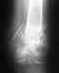

Re: эндопротезирование голеностопного сустава